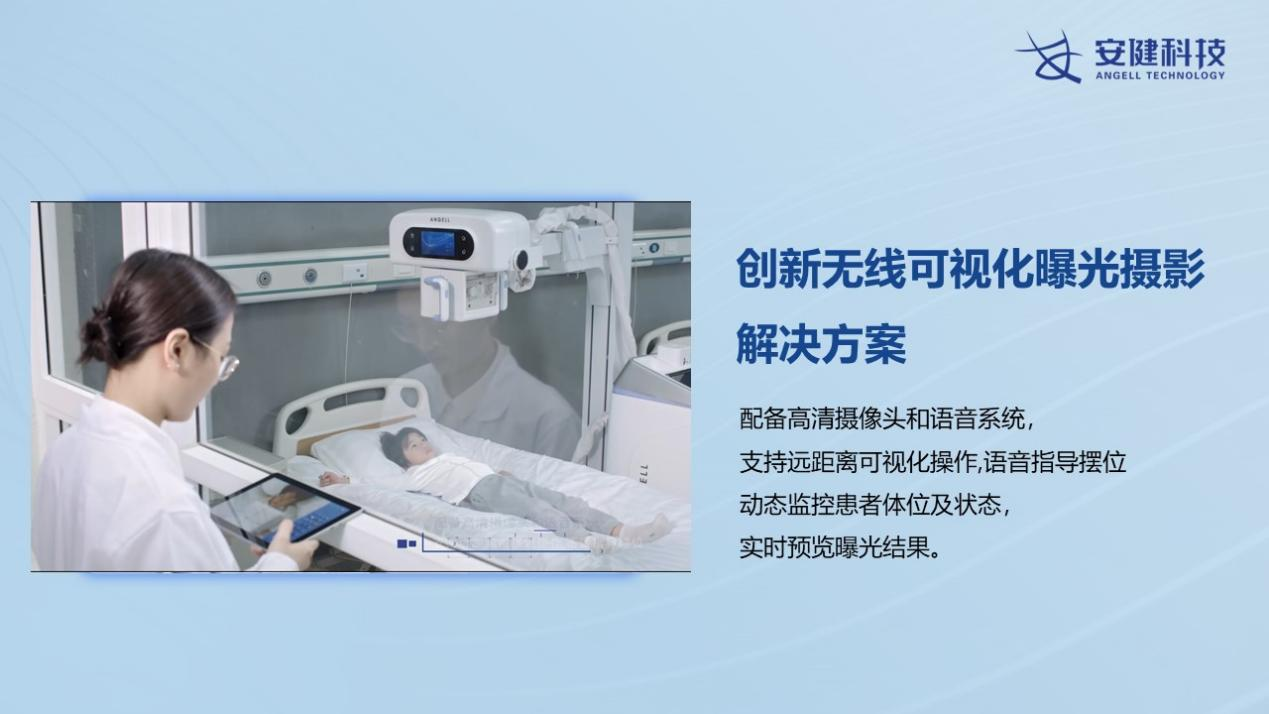

伴随数字化X线摄影技术发展与进步,X线摄影检查在灵敏度、曝光宽容度以及影像清晰度等方面,都有巨大的进步。数字化X线摄影检查在临床具备广泛的应用价值,其中,移动DR由于其良好的移动性能,可满足床旁摄片。摄片流程简单、快捷、便利、安全,在临床上具有多种应用价值。包括如重症患者、重症新生儿患者以及术后不能搬动的患者,以及那些需要骨折牵引和老年体衰患者,通过移动DR的近床摄片都是最佳选择。当前的移动DR支持无线可视化曝光摄影,极大提升摄片效率同时能大幅减少X线辐射影响。

除了百微平板的极大优势之外,飞燕移动DR采用了无线曝光与可视化曝光摄影解决方案,支持SID智能识别与调控,减少了影像技师摆位摄片的时间,也减少了由于线缆可能对重症插管患者所带来的医疗事故风险。此外,传统不可视化曝光的操作特点,在如SARS、COVID-19此类病毒性感染场景中,由于病情发展变化较快,重症患者需每日摄片了解病情,病情轻者则隔日摄片工作量大,放射操作人员所接受的辐射剂量多。通过可视化曝光,减少了对患者及操作技师的辐射次数,检查耗时缩短,减少了技师与患者的接触时间,在对传染性疾病患者检查时,降低了医技工作人员的感染几率。